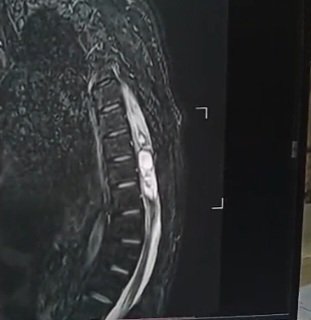

Case I performed recently.